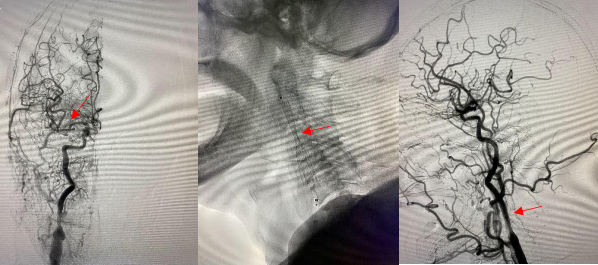

头颈部血管造影提示:患者为右侧颈内动脉极重度狭窄合并右侧大脑中动脉闭塞。

由远及近,优先开通右侧大脑中动脉恢复颅内血流,再行右侧颈内动脉起始部支架植入血管成形,顺利开通闭塞血管,颅内血流恢复。

经肱动脉穿刺入路进行机械取栓开通颅内闭塞大血管,在标准股动脉穿刺入路困难或无法穿刺的情况下,急诊经肱动脉入路,缩短到达颅内病变的距离和时间,可谓“另辟蹊径,智取华山”。目前,经肱动脉穿刺入路行机械取栓术,在国内文献报道例数极少。而我院脑血管病治疗中心已开展常规经桡动脉入路行机械取栓,而经肱动脉入路行机械取栓的成功开展,再次填补渭南地区介入治疗技术空白,使我院AIS机械取栓技术位居省内前列。科室医护团队紧跟国内外最新诊疗指南,在渭南地区率先开展机械取栓治疗急性脑梗塞,为患者提供“一站化、规范化、流程化”脑卒中诊疗模式。